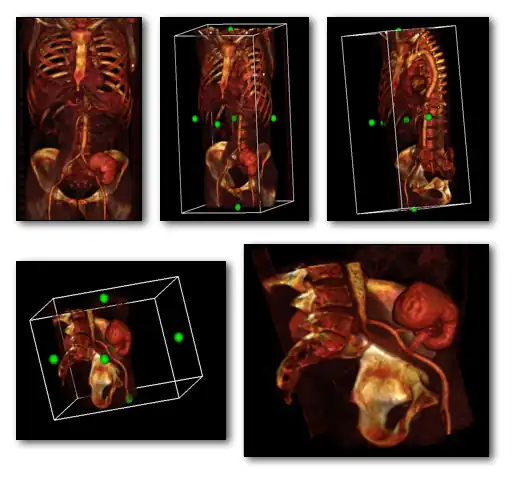

A final feature to note about volume rendering is that 3D editing techniques can be applied so as to exclude unwanted features from the computations and to expose internal structure. This is illustrated in the following figure, where planes of an orthogonal frame can be moved to crop the voxel data from six directions.

3D volume rendering with cropping frame (left) and cropped, magnified projection (right).